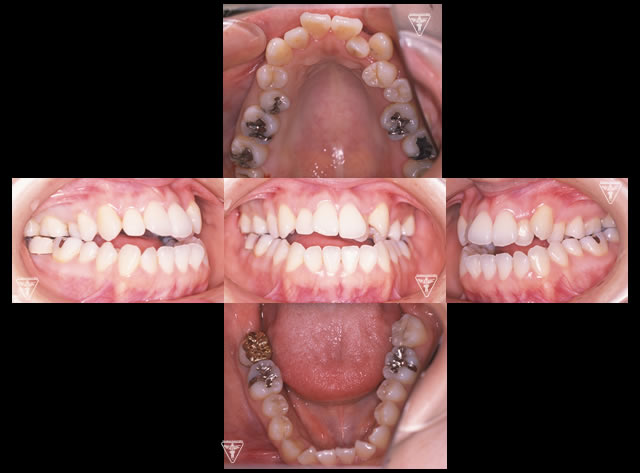

20代女性:オープンバイト(開咬)をゴムメタルにて矯正治療したケース

オープンバイトは、上下の歯を噛み合わせた時に奥歯は噛んでも前歯が噛まない歯列不正の1つです。

治療前、装置装着直後

治療後

治療前後の比較